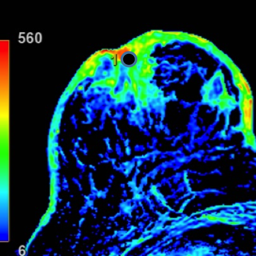

2. Describe los hallazgos por RM:

- A. Cambios en MD en relación con cuadrantectomía previa sin realces sospechosos.

- B. Cambios posquirúrgicos en MD con realce tipo no masa en región retroareolar con curvas funcionales inespecíficas (tipo 1).

- C. Engrosamiento cutáneo en CCII de MD con realce heterogéneo nodular asociado a un realce tipo no masa retroareolar con curvas funcionales sospechosas (tipo 2).

- D. Engrosamiento cutáneo y retracción de complejo areola pezón (CAP) de MD con múltiples realces nodulares retroareolares de distribución ductal con curvas funcionales inespecíficas (tipo 1).

- E. Engrosamiento cutáneo post-radioterapia en MD sin otros hallazgos sospechosos.